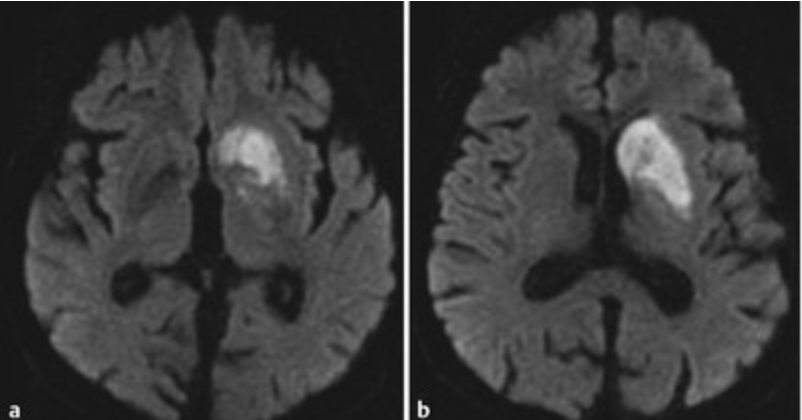

What vessel(s) caused this stroke?

Anterior Choroidal Artery

Occlusion of which vessel(s) cause this stroke?

Artery of Percheron